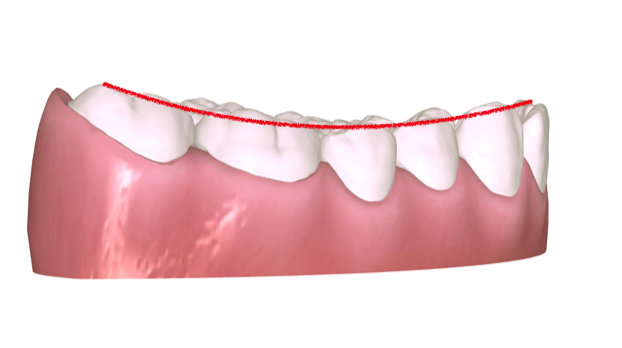

上下颌初始与终末位置重叠。上颌以21为基准内收6㎜(如图1-11所示),下颌以31为基准内收3㎜(如图1-12所示)。内收过程当中要时刻关注前牙支抗(是否出现前牙唇倾)要根据前牙支抗情况,选择不同⼒值的皮筋牵引,需要注意的是,合理的移动序列比支抗钉更加重要。关注前牙支抗的同时也要关注后牙段,防⽌已经推到位的磨牙出现近中移动,有效的⽅法是在已经到位的磨牙制作TPA或使用间接支抗(如图1-12所示)。垂直向:该患者为均角,设计为通过伸长前磨牙压低后牙与下前牙整平下颌SPEE曲线,前牙正常覆合结束。SPEE曲线整平⽅式:对于⾼角患者、后部HE平面较陡的SPEE曲线主要通过压低后牙的⽅式整平。均角患者设计压低后牙与下前牙,伸长前磨牙的⽅式整平,低角患者希望更多通过升⾼后牙的⽅式整平SPEE曲线。⽔平向:以16、26为基准,不设计扩弓调整上下颌牙弓宽度。第⼀:参考Wala嵴(如图1-14所示),看颊侧是否有⾜够的骨量,通过测量FA点与 Wala Radge 的距离或参考CBCT进⾏判断)、磨牙的转矩(如图1-14所示),可以在电⼦扫描模型中的后视图当中进⾏观察(如图1-15)。后牙舌倾是扩弓的有利条件。如果磨牙已经是颊倾的状态,则不建议再设计扩弓,可在处⽅表当中向技师表明“以 16、26横向宽度为基准,维持现在的磨牙牙弓宽度”。